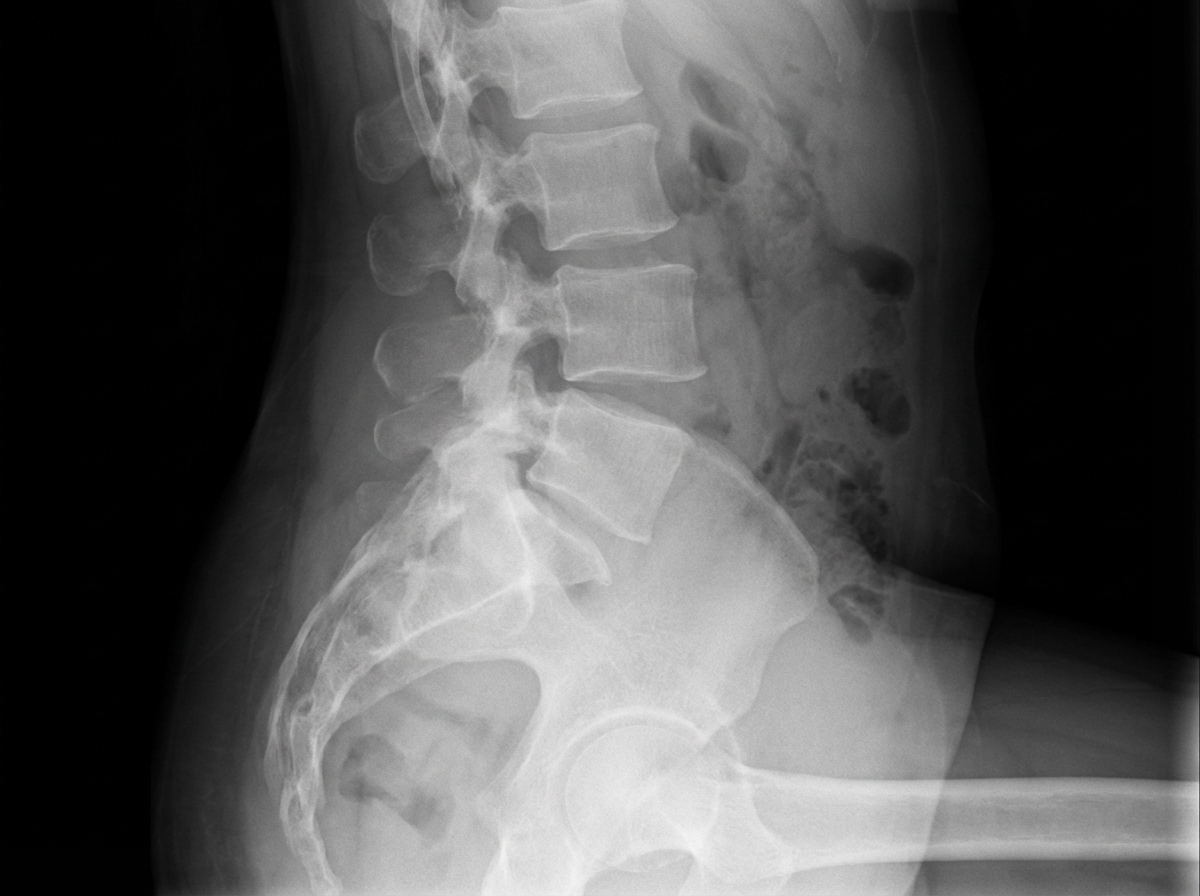

The following X-ray was taken of a 50-year-old female with chronic backache. What is the most likely diagnosis?

Explanation: ***Spondylolisthesis*** - **Anterior vertebral slippage** creating a **step-ladder deformity** on lateral lumbar spine X-ray is pathognomonic for spondylolisthesis. - The **Meyerding grading system** can classify the degree of slippage based on the percentage of vertebral body displacement forward. *Spondylolysis* - Refers to a **pars interarticularis defect** (stress fracture) without vertebral slippage, appearing as a **"collar on Scotty dog"** on oblique views. - Would not show the characteristic **anterior displacement** of one vertebra over another seen in this case. *Spondylosis* - Represents **degenerative changes** including **osteophyte formation** and **disc space narrowing** without vertebral slippage. - X-ray would show **joint space narrowing** and **bone spurs** rather than the step-ladder deformity of vertebral displacement. *Prolapsed inter-vertebral disc* - A **soft tissue abnormality** that is **not directly visible** on plain X-rays and requires MRI for visualization. - May show secondary signs like **reduced disc height** but would not demonstrate the clear **vertebral slippage** pattern seen here.